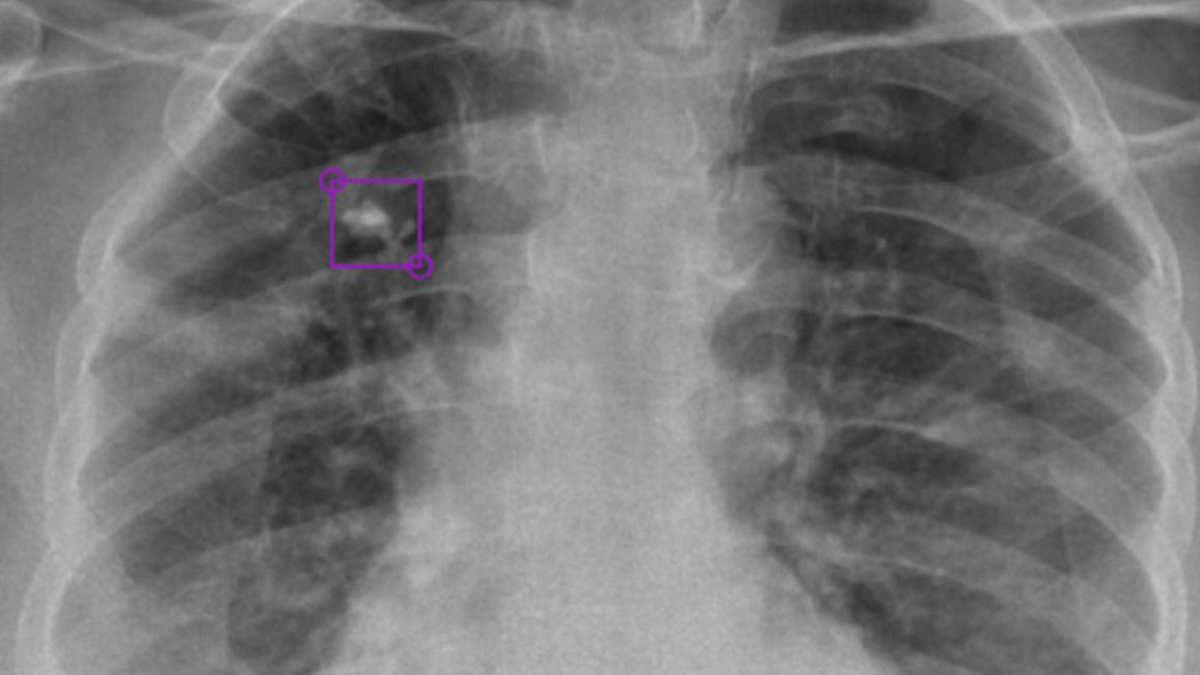

Medical Imaging Augmented With Ai Nvidia